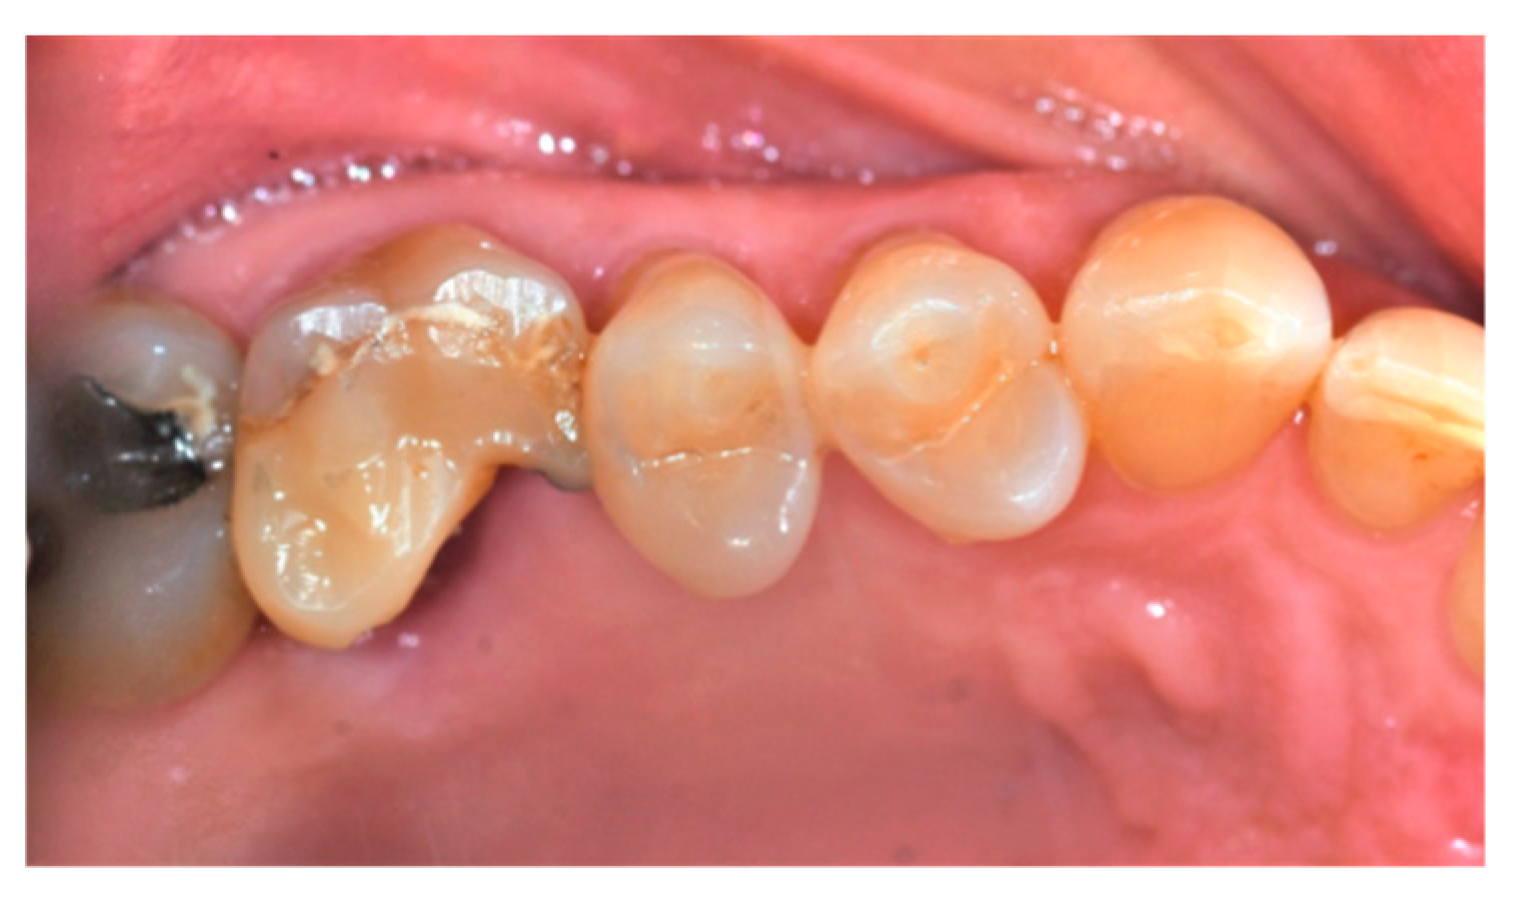

- Location of the dental element(s) to be extracted;

- Cause of extraction: caries, orthodontic reasons, or trauma;